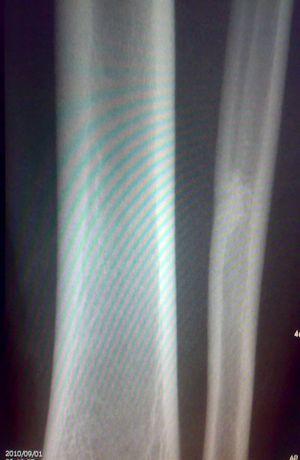

标题: X7846:M 20岁 外伤来诊。良性骨肿瘤吗? [打印本页]

标题: X7846:M 20岁 外伤来诊。良性骨肿瘤吗?

腓骨中下段骨皮质下不规则高密度影,侧位呈水滴形。外伤,估计平时没有症状,结合病人年龄,支持纤维性骨皮质缺损

怎么那么人考虑“局限性骨皮质缺损愈合修复后改变”呢?再说骨外膜成骨较内膜成骨多见。我觉得只是一种“骨纤维构不良”或只是“骨岛”。没多大意义。